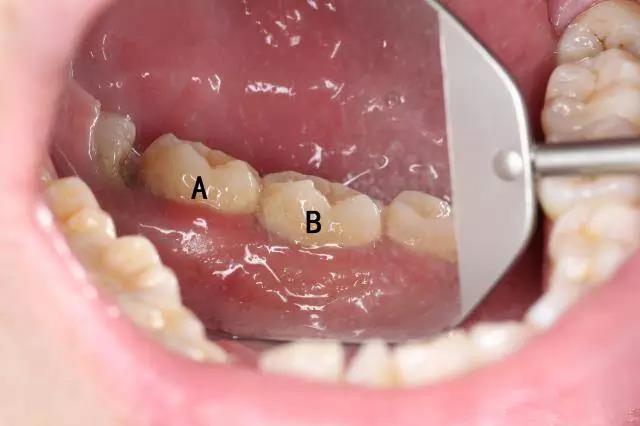

有些人就会纠结,感觉洗牙后牙齿中间空空的,牙缝比以前大了,这是怎么回事?小编想说的是,牙缝变大只是一种视觉现象,真正的原因是他们本身的牙石较多,当你洗牙后,这些牙石被清洁掉,原本被牙石占据的空间露出来了,所以洗牙后牙缝变大说明你本身就存在牙周疾病,要开始引起重视了。

如果牙齿表面有凹坑,说明有两种可能,一是刷牙不当的牙齿会出现楔状缺损;二是喝碳酸饮料过多会腐蚀牙齿,牙颈部形成缺口。千万不能忽视!这些症状容易引起牙齿敏感,而洗牙有办法,一般洗完抛光后,将这些粗糙小凹坑修平整,所以洗牙并不会破坏牙齿。